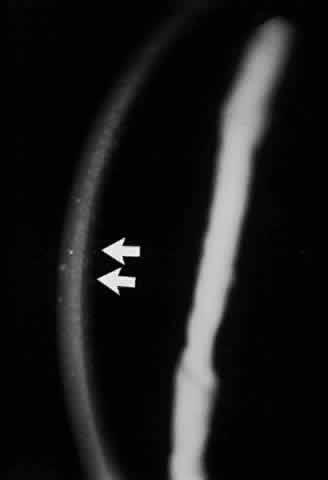

Conjunctival involvement in epidermolysis bullosa begins with vesicle formation, leading to ulceration and symblepharon formation.107 In the cornea, recurrent erosions occur that lead to vascularized scars (Fig. 18). Histologically, the epithelium exhibits vacuolation, particularly of the basal cell layer. The epithelium is poorly adherent to Bowman's membrane, whereas the remainder of the corneal structure is essentially normal.108 McDonnell reported that 8 of 11 patients with the dystrophic form of epidermolysis bullosa had ocular abnormalities, including conjunctival shrinkage, with symblepharon formation and corneal opacities.109 The authors remarked that these abnormalities were slowly progressive, and that except for recurrent corneal erosion, the patients were ocularly asymptomatic. Other ocular histopathologic changes have been noted in epidermolysis bullosa letalis by Aurora and co-workers.110 They have described a patient exhibiting edema of the trabeculum, iris, ciliary body, lens, and optic nerve. Focal edema and necrosis of the choroid and retina as well as total retinal detachment were also present in this patient. Citing research by other workers, these authors suggest that some of the ocular changes observed in epidermolysis bullosa may be due to focal accumulation of a proteolytic enzyme, possibly collagenase. Zierhut and associates, using modern criteria for the definitive diagnosis of epidermolysis bullosa acquisita (EBA), reported the case history of a 23-year-old man with EBA who developed bilateral tiny corneal subepithelial vesicles.111

Fig. 18. Ectropion and corneal ulcer in epidermolysis bullosa. (Courtesy of Dr. GR Beauchamp)